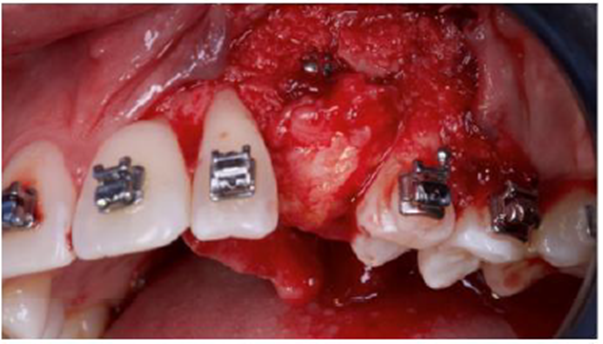

Dois blocos foram fixados frouxamente da região canina vestibular e palatina com dois parafusos de osteossíntese de 1,5 x 10 mm (parafusos Orth – Implacil De Bortoli, São Paulo – Brasil) e o osso particulado foi inserido no espaço entre as placas (Figuras 9 a 12 ).